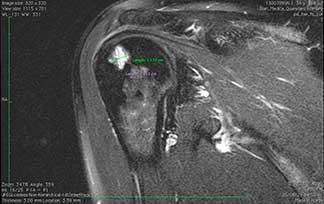

Artroscopia

de hombro

Permite ver la articulación del hombro a través de tres portales menores a un centímetro de diámetro lo cual permite corroborar los diagnósticos y aplicar tratamientos curativos ya que la mayoría de las estructuras del hombro son accesibles por artroscopia. Es una técnica mínimamente invasiva para acceder a los dos compartimentos de la articulación la glenohumeral y subacromial.

¿Por qué se realiza?

Es una opción de tratamiento en las patologías del manguito rotador (supraespinoso, subescapular, infraespinoso y redondo mayor), tendinitis de la porción larga del biceps, compresiones subacromiales, inestabilidad glenohumeral y algunos tipos de fracturas o luxaciones.